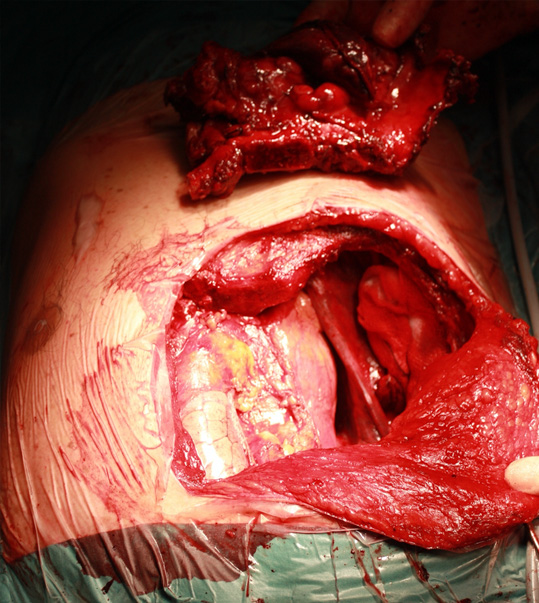

Warning: contains images of surgery

The intraoperative images show removal of a malignant tumour involving the sternum and several ribs and the subsequent repair and reconstruction of the chest wall (from left to right).